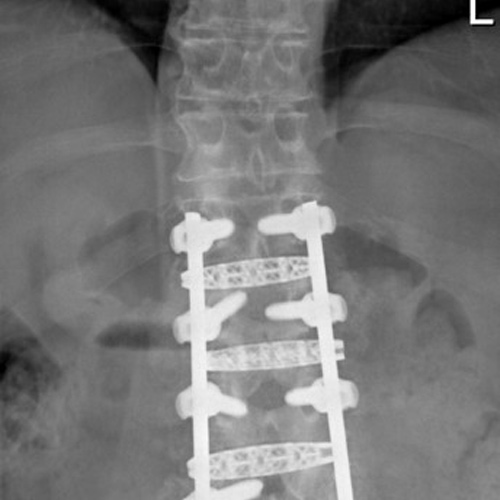

Spinal stenosis (Lumbar) Spinal stenosis (Cervical) Spinal stenosis (Thoracic) Lumbar Disc Herniation Spondylolisthesis Cervical Foraminal Stenosis Vertebroplasty Lumbar Fusion Anterior Cervical Fusion (ACDF) Posterior Cervical Fusion Thoracic Fusion Revision Lumbar Fusion Surgery Facet Joint Cyst Spinal Tumour Minimally Invasive Lumbar Fusion (XLIF) Minimally Invasive Lumbar Fusion (ALIF) Lumbar Fusion (TLIF) Thoraco-lumbar Fusion Lumbar Corpectomy Complex Lumbar Spine Surgery (Spino-pelvic fixation) Complex Cervical Spine Surgery Complex Thoracic Spine Surgery Occipito-cervical Fusion Minimally invasive surgery for thoracic disc herniation Other Related Topics